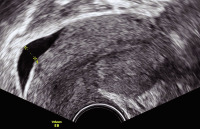

Tipps und Tricks im Gyn-Ultraschall: Das prämenstruelle und das menstruelle Endometrium

Journal für Gynäkologische Endokrinologie 2013; 7 (3) (Ausgabe für Österreich): 24-25 Journal für Gynäkologische Endokrinologie 2013; 7 (3) (Ausgabe für Schweiz): 33-34 Volltext (PDF) Abbildungen